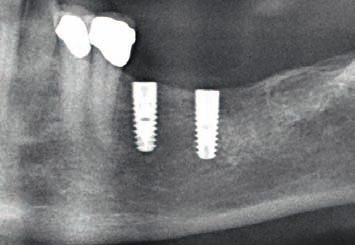

Исследование на рентгене после имплантации зубов

Раздел: Снимки-откровения